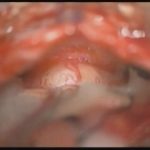

術中写真

摘出 前